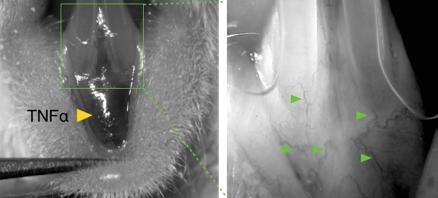

TNFα injected in the mandibular buccal gingival between incisors acts as pro-inflammatory stimulus that triggers leukocyte infiltration and gingival inflammation.  Labeled leukocytes are tracked from intravascular to extravascular compartment by intravital microscopy.

At sites of inflammation TNFα induces increased vascular permeability and upregulation of adhesion molecules in leukocytes and endothelial cells to enhance leukocyte recruitment.   Acute gingival inflammation is induced in mandibular incisor region by injection of TNFα in alveolar mucosa on midline.   Leukocytes are labeled 2 h after induction of inflammation by IV delivery of rhodamine 6G (R6G) or specific antibodies.

Left: Leukocye-endothelium interactions were assessed in the area coronal to the site of TNFα delivery, between the mandibular incisors.

Right: Several post-capilary venules were selected for microscopic visualization (green arrows).